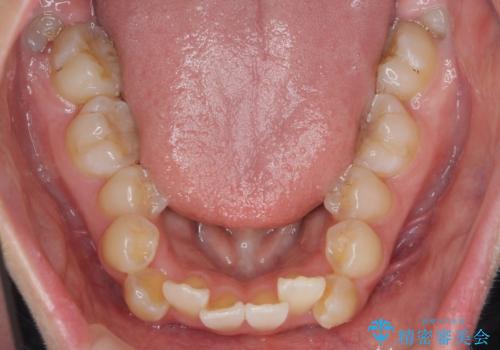

突き出た前歯を治したい 小臼歯抜歯+マルチブラケット矯正

- 突き出て、気になる前歯の角度の改善を求めて来院されました。

前歯の角度を改善するために小臼歯4本の抜歯を行いワイヤー マルチブラケットを用いて、しっかりと前歯の角度を改善する治療計画としました。